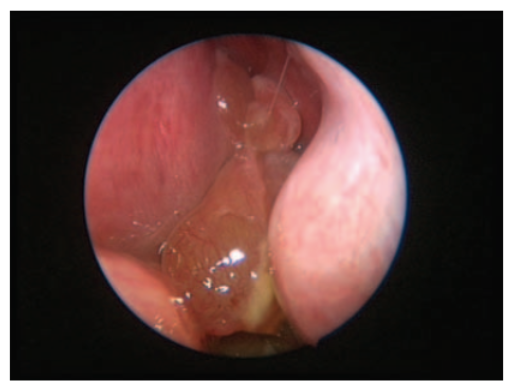

Nút mô-nhầy vùng mũi

Đây là hình ảnh từ một ca phẫu thuật nội soi trong mũi.